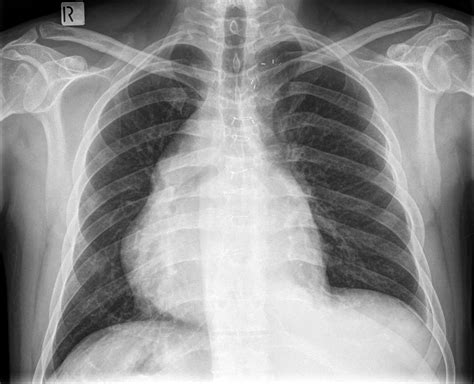

• Chest X-ray: This is often the first diagnostic test performed. It can show the position of the mediastinum and any abnormalities in the lungs or pleural space.

• mediastinal shift x ray

• mediastinal shift to the right